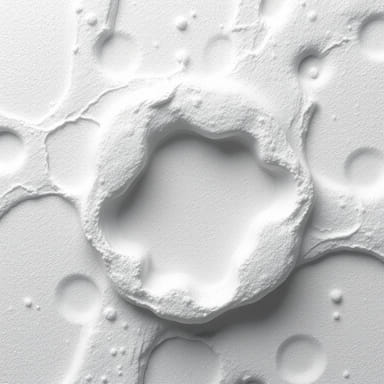

Appearance of Granulation Tissue

Clinically, granulation tissue is recognized by its moist, bumpy surface that looks somewhat like small red granules, hence the name. The redness comes from the dense network of capillaries, while its soft consistency reflects the presence of newly formed connective tissue. A healthy wound usually shows bright red granulation tissue, which is a positive sign of progress toward closure.